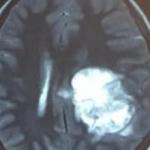

عمده تومور های بدخیم این نواحی، تومور های متاستاتیک یا تومور هایی هستند که از نواحی مختلف مثل نواحی سینوس های پرانازال یا بینی به قاعده ی جمجمه دست اندازی می کنند و روش های درمان آن فقط برداشت بیوپسی در اکثر مواقع و انجام رادیوتراپی است.

اما مشکل عمده ی این نواحی تومور های خوش خیم هستند. تومور هایی مثل تومور های حفره ی چشم، تومور های ناحیه هیپوفیز و تومور های ناحیه ی سی پی انگل یا ناحیه ی مغزی مخچه ای مثل نورینوم آکوستیک. این تومور ها خوش خیم هستند و بیماران در صورت برداشت این تومور ها توسط جراح می توانند سال های زیادی زندگی کنند.